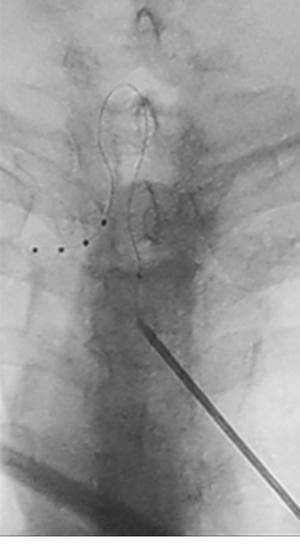

Figura 1

Figura 2

Figura 3

Figura 4

Figura 5

Figura 6

Figura 7